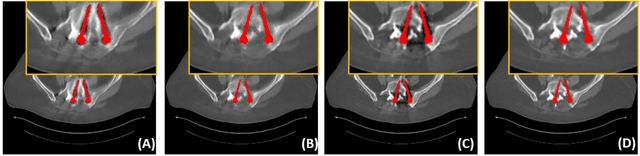

Abstract:Metal implants can heavily attenuate X-rays in computed tomography (CT) scans, leading to severe artifacts in reconstructed images, which significantly jeopardize image quality and negatively impact subsequent diagnoses and treatment planning. With the rapid development of deep learning in the field of medical imaging, several network models have been proposed for metal artifact reduction (MAR) in CT. Despite the encouraging results achieved by these methods, there is still much room to further improve performance. In this paper, a novel Dual-domain Adaptive-scaling Non-local network (DAN-Net) for MAR. We correct the corrupted sinogram using adaptive scaling first to preserve more tissue and bone details as a more informative input. Then, an end-to-end dual-domain network is adopted to successively process the sinogram and its corresponding reconstructed image generated by the analytical reconstruction layer. In addition, to better suppress the existing artifacts and restrain the potential secondary artifacts caused by inaccurate results of the sinogram-domain network, a novel residual sinogram learning strategy and nonlocal module are leveraged in the proposed network model. In the experiments, the proposed DAN-Net demonstrates performance competitive with several state-of-the-art MAR methods in both qualitative and quantitative aspects.